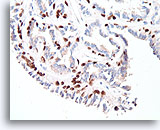

Papillair carcinoom, Borst FNA, Celblok.

Een immunokleuring met p63 voor myoepitheliale cellen is ook negatief bij de patiënt die in voorgaande afbeeldingen getoond is; dit steunt de diagnose van papillair carcinoom.

10X

Papillair carcinoom, Borst FNA, Celblok.

Een immunokleuring met p63 voor myoepitheliale cellen is ook negatief bij de patiënt die in voorgaande afbeeldingen getoond is; dit steunt de diagnose van papillair carcinoom.

10X